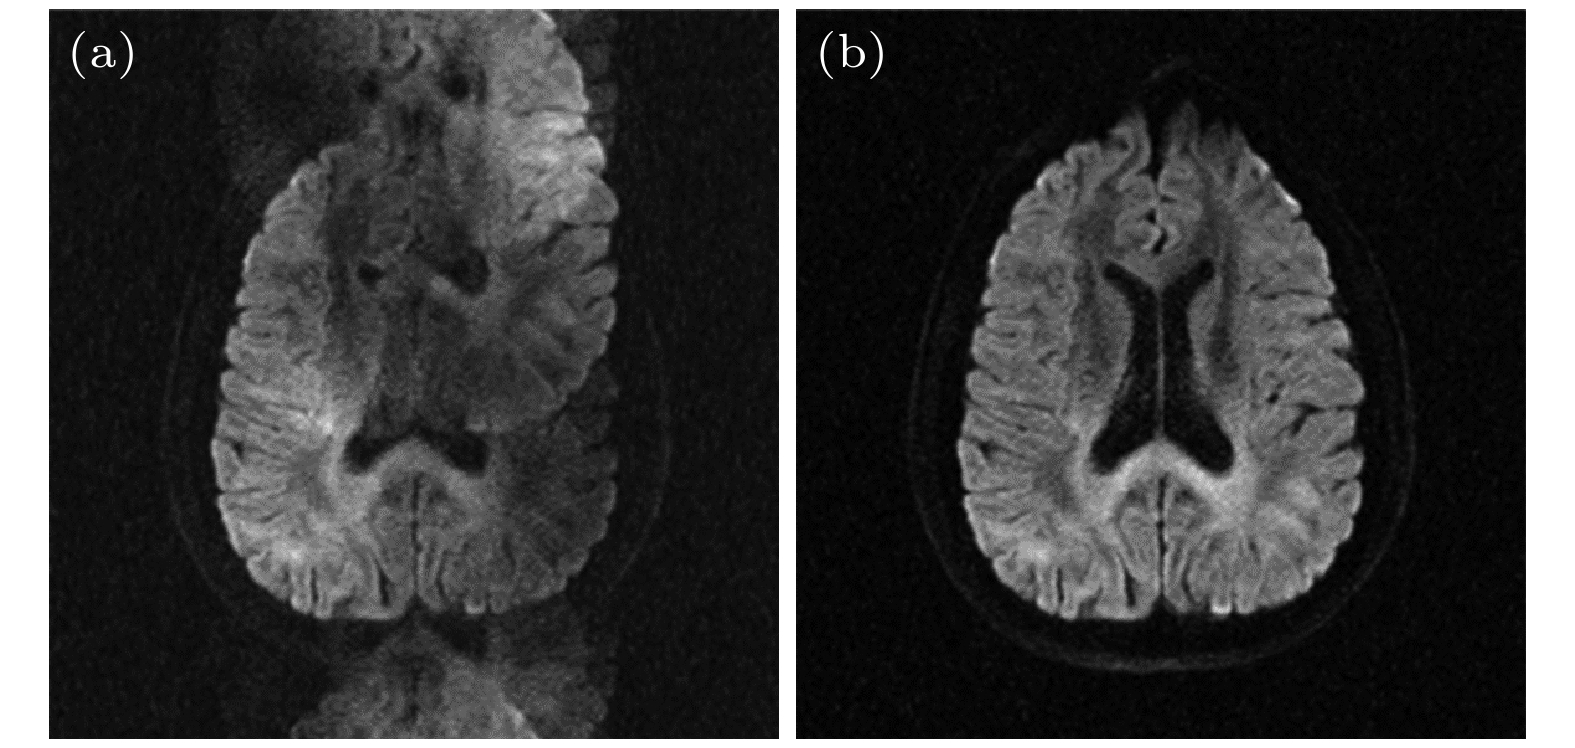

磁共振扩散加权成像(DWI)在神经科学和临床疾病诊断中具有重要价值. 单次激发平面回波成像(ss-EPI)是DWI最常用的技术, 但受主磁场不均匀性和T2/T2*衰减的影响, 易出现几何变形、信噪比低等问题. 为解决这些问题, 研究者开发了更先进的高分辨率磁共振扩散成像技术. 本文对这些成像技术进行综述. 平面回波成像(EPI)方面, 本文介绍了读出分段EPI、交错采集EPI、点扩散函数编码EPI、EPTI等多次激发EPI DWI技术, 这些技术能够减小或消除几何变形、提高图像信噪比和分辨率. 此外, 多次激发EPI与多层同时激发技术(SMS)的结合能够缩短采集时间, 本文对此类技术进行简要介绍. 相较于EPI, spiral成像的信噪比和采样效率更高, 但对主磁场不均匀性更敏感. 在spiral成像部分, 本文分别介绍了单次激发以及多次激发的spiral DWI成像, 以及二者与SMS技术的结合. 本文重点介绍了各类成像技术的原理、采集策略与重建方法. 最后, 本文阐述了高分辨率扩散成像的挑战和未来方向, 包括三维DWI、体部DWI、磁场探针、超强梯度磁共振系统以及超高场磁共振系统.Diffusion-weighted magnetic resonance imaging (DWI) holds significant value in neuroscience and clinical disease diagnosis. The most commonly used single-shot echo-planar imaging (EPI) for DWI is affected by static magnetic field (B0) inhomogeneity and T2/T2* decay, leading to geometric distortion, low signal-to-noise ratio (SNR), etc. To solve these problems, researchers have developed more advanced high-resolution diffusion MRI techniques. This article comprehensively reviews these imaging methods. In the context of echo-planar imaging (EPI), this review covers multi-shot EPI-based DWI techniques, including readout-segmented EPI (RS-EPI), interleaved EPI (iEPI), point spread function-encoded EPI (PSF-EPI), and echo-planar time-resolved imaging (EPTI). These methods effectively reduce or eliminate geometric distortions while improving SNR and spatial resolution. Additionally, the combination of multi-shot EPI with simultaneous multi-slice (SMS) acquisition can shorten scan time, which is also briefly discussed in this article. Compared with EPI, spiral imaging offers higher SNR and sampling efficiency but is more sensitive to B0 inhomogeneity. In the spiral imaging section, we review single-shot spiral DWI and multi-shot spiral DWI, as well as their integration with SMS techniques. This article emphasizes the concepts, acquisition strategies, and reconstruction methods of these imaging techniques. Finally, we discuss the challenges and future directions of high-resolution diffusion imaging, including 3D DWI, body DWI, magnetic field probes, ultra-high gradient systems, and ultra-high-field MRI systems.